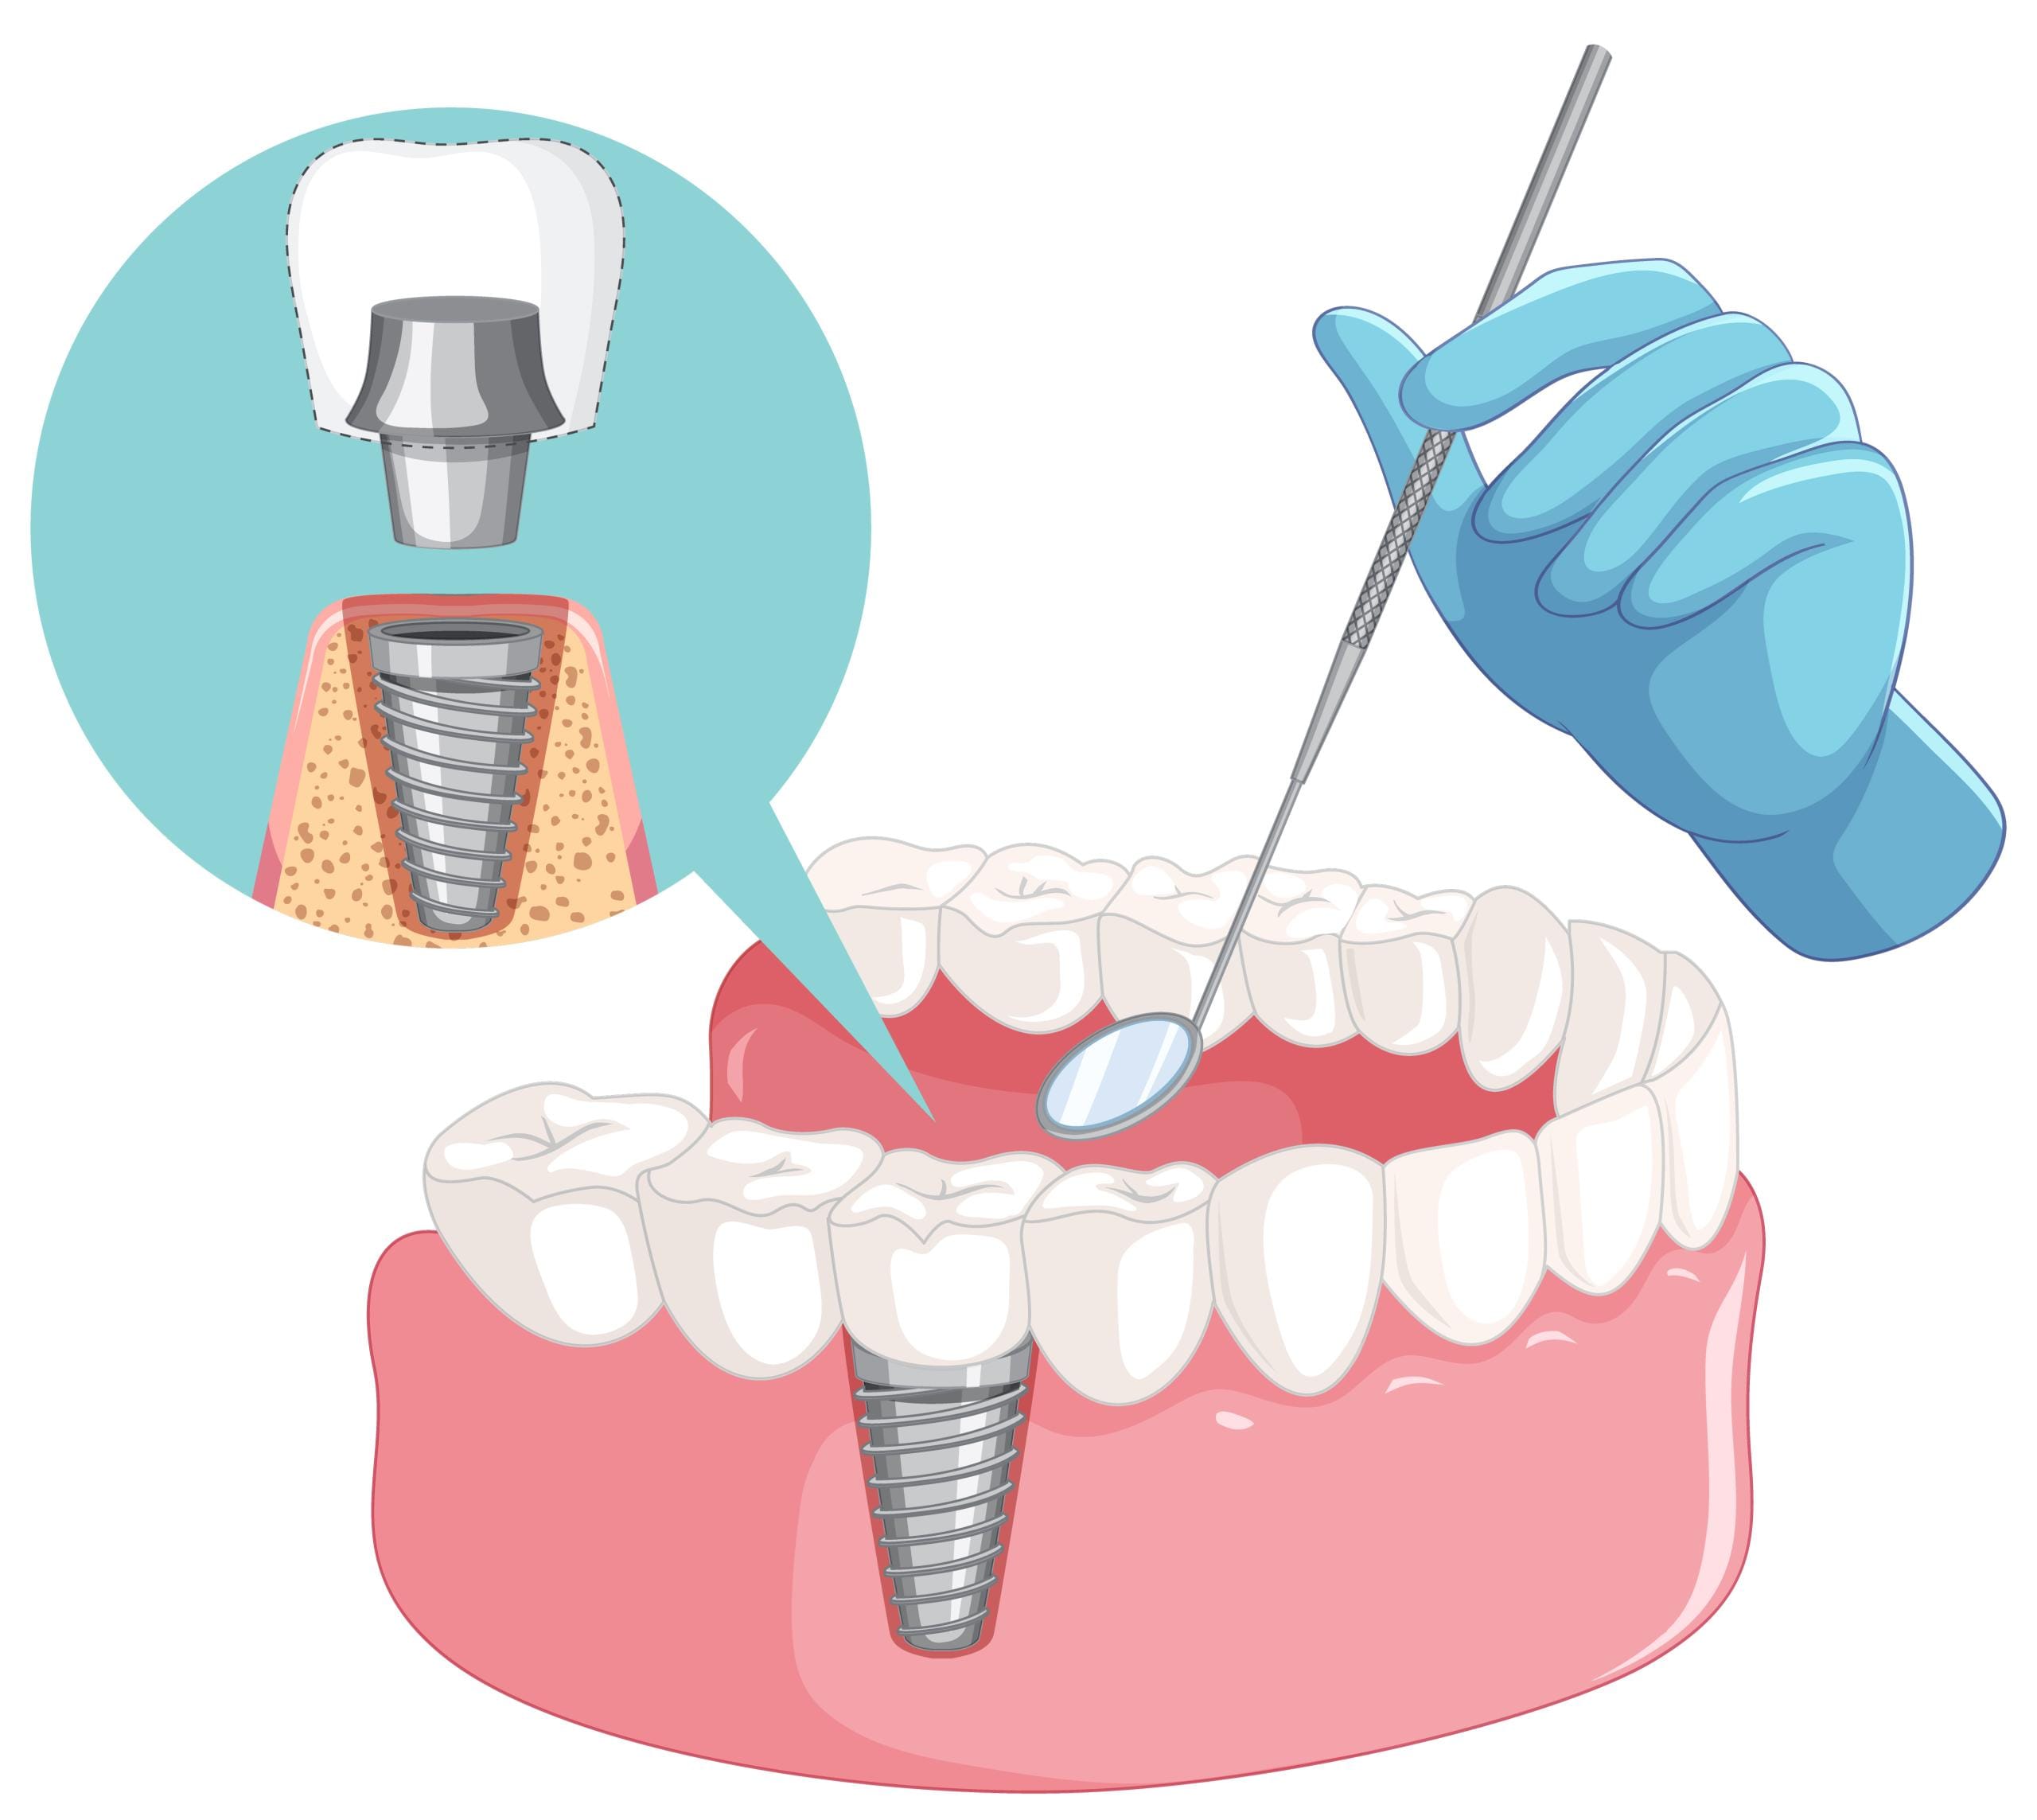

They are like little titanium posts that are surgically implanted into your jawbone to mimic missing roots of teeth. When the implant bonds to your bone-weight, it serves as a secure base for keeping new replacement teeth-including crowns, bridges, or dentures-in place.

Titanium posts that were surgically inserted within the jaw bone under local anesthesia or sedation for your comfort.

This healing normally takes several months while the bone grows around the implant, helping to stabilize it.

Abutment & Crown Placement

A crown that is custom-made to match your natural teeth is then attached to the implant.